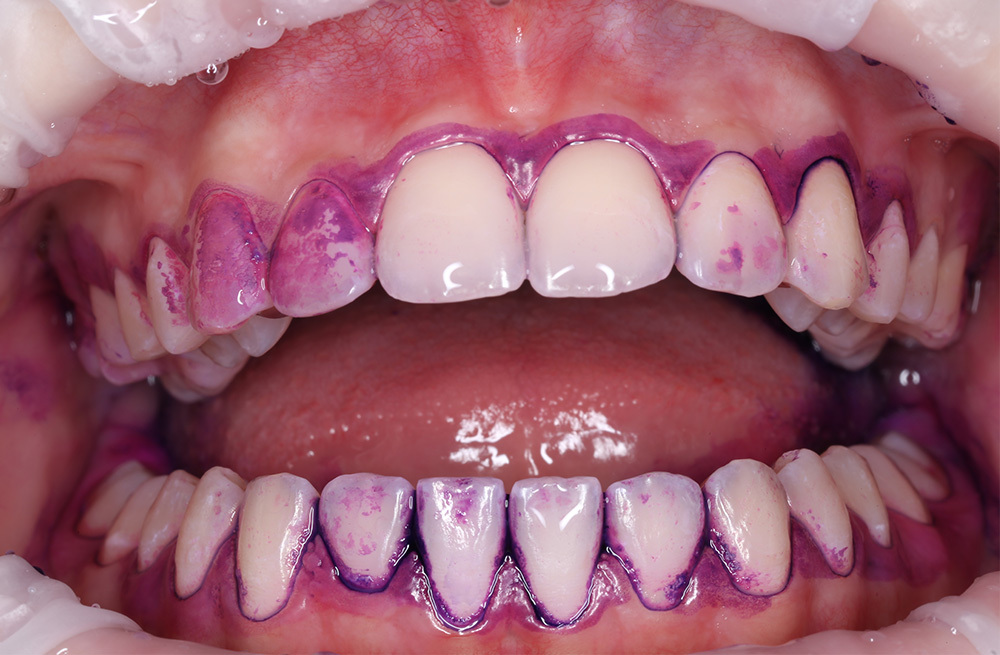

Удаление мягкого и пигментированного налёта у подростка с использованием Air-flow